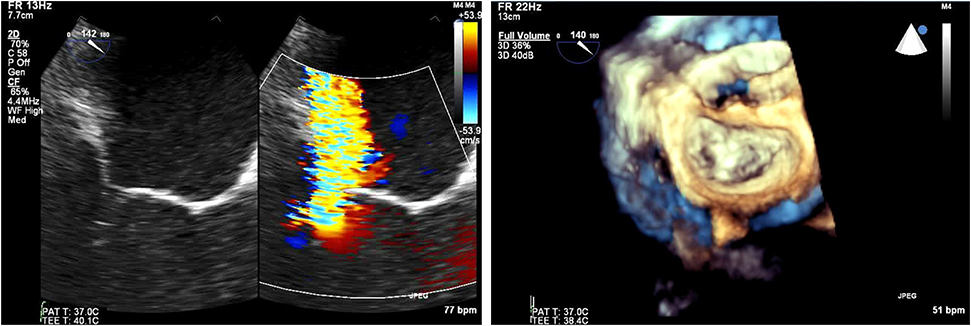

For mixed MVD or pure mitral regurgitation, the development of 3D TEE has allowed us the reconstruction of the mitral valve in a similar way as the surgeon would view this in the operating room (Figure 3). Another important feature and still a matter of debate is the identification of clefts and their differences to indentations, in myxomatous mitral disease. The deep cleft-like indentations are frequent on the posterior side of the mitral valve and are easily identified with 3D TEE—thus require closure during transcatheter valve repair (Figure 4). Anatomically, they are not related to excess annular enlargement or prolapse, butas an outcome of single scallop prolapse with paucity of the tissue and greater separation between the scallops (10).

Figure 3. Pre-procedural evaluation for MitraClip: clockwise imaging: (a) mid-esophageal view 0 degrees demonstrating severe mitral regurgitation (b) 3D-TEE surgical view with a posterior cleft like indentation (c) mid-esophageal view 90 degrees—commissural view: severe mitral regurgitation (d) 3D-TEE with color demonstrating the regurgitation through the coaptation gap (e) continuous wave Doppler across mitral valve (f) pulmonary vein signal—pulsed wave Doppler.

Figure 4. (Left) Tranesophageal echocardiography at 140 degrees for the evaluation of severe mitral regurgitation—(right) MitraClip positioning and 3D- transesophageal surgical view.

For edge to edge repair, the bicaval view is important for the advancement of the steerable guide catheter while all TEE planes focusing on the mitral valve are important for the advancement of MitraClip in the left ventricle and the grasping of the leaflets. It is recommended to initially close the MitraClip only up to 60–90° and aim for a full closure of the Clip only after determination of proper leaflet insertion and demonstration of MR reduction. For assessment of proper leaflet insertion into the MitraClip multiple planes are useful. The insertion of the posterior leaflet is commonly best seen in the LVOT view, and the insertion of the anterior leaflet in the four-chamber view. The intercommissural view can add information such as entrapped chordae tendinae which may be visible at the free edges. Once the leaflets appear securely inserted and well-positioned in between the Clip arms and the grippers and some reduction in mitral regurgitation is documented, the MitraClip can be fully closed. An example of preprocedural imaging for MitraClip is demonstrated on Figure 3 while another example of positioning is demonstrated on Figure 4.